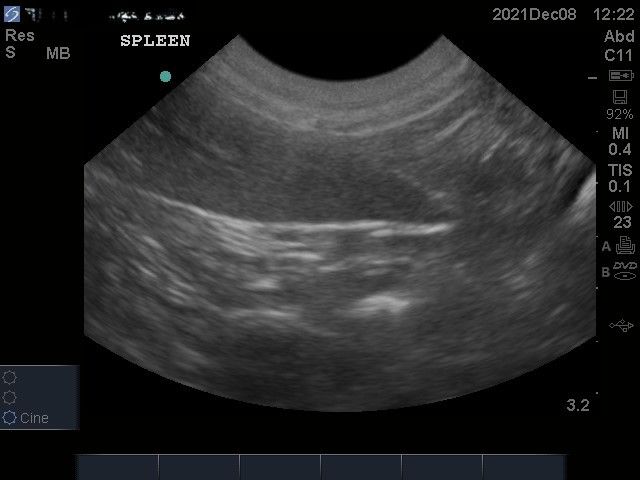

I have used the C11x probe (5-8MHz) which has been good for abdominal scanning of cats, small dogs and basic echocardiography. The depth obtainable (13cm) on the probe I have used is disappointing for large dogs. Having said that the image quality is reasonable. I have not been able to source new prices for this machine (if you are selling them please do get in touch!), however one machine I saw being sold second hand was well under £10,000 which suggests it’s starting price is <£10,000.

Images from the M Turbo